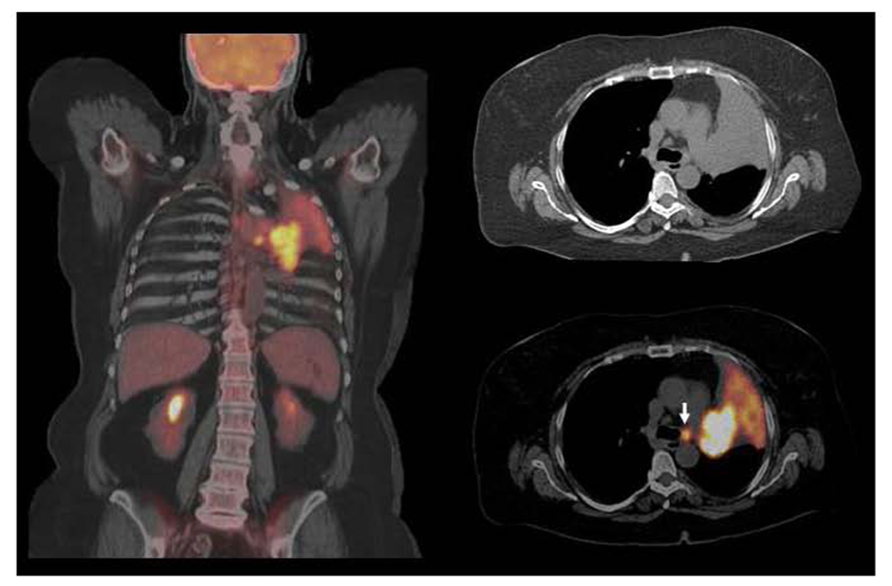

![PET/CT images of [18F]FEAU accumulation in the anterior... | Download ...](https://www.researchgate.net/profile/Frank-Marini/publication/51632738/figure/fig4/AS:213402938023945@1427890633931/PET-CT-images-of-18FFEAU-accumulation-in-the-anterior-interventricular-lymphatic-trunk.png)